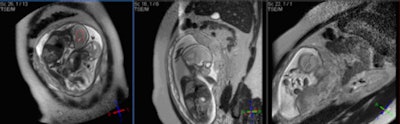

Fetal MR spectroscopy can assist with in utero measurements of fetal cerebral lactate concentrations. It may provide information on the adequacy of fetal oxygenation, and can help with decision-making on the optimal time of delivery. This figure shows fetal localizers used for spectroscopy measurements. Image courtesy of Janet De Wilde, PhD, and C. McComb."In the pre-examination questionnaire for determination of pregnancy, it is important to ask two questions: What was the first day of your last complete menstrual period? To the best of your knowledge, are you pregnant, or do you think you could be?" he said during last year's ECR refresher course on pregnancy.